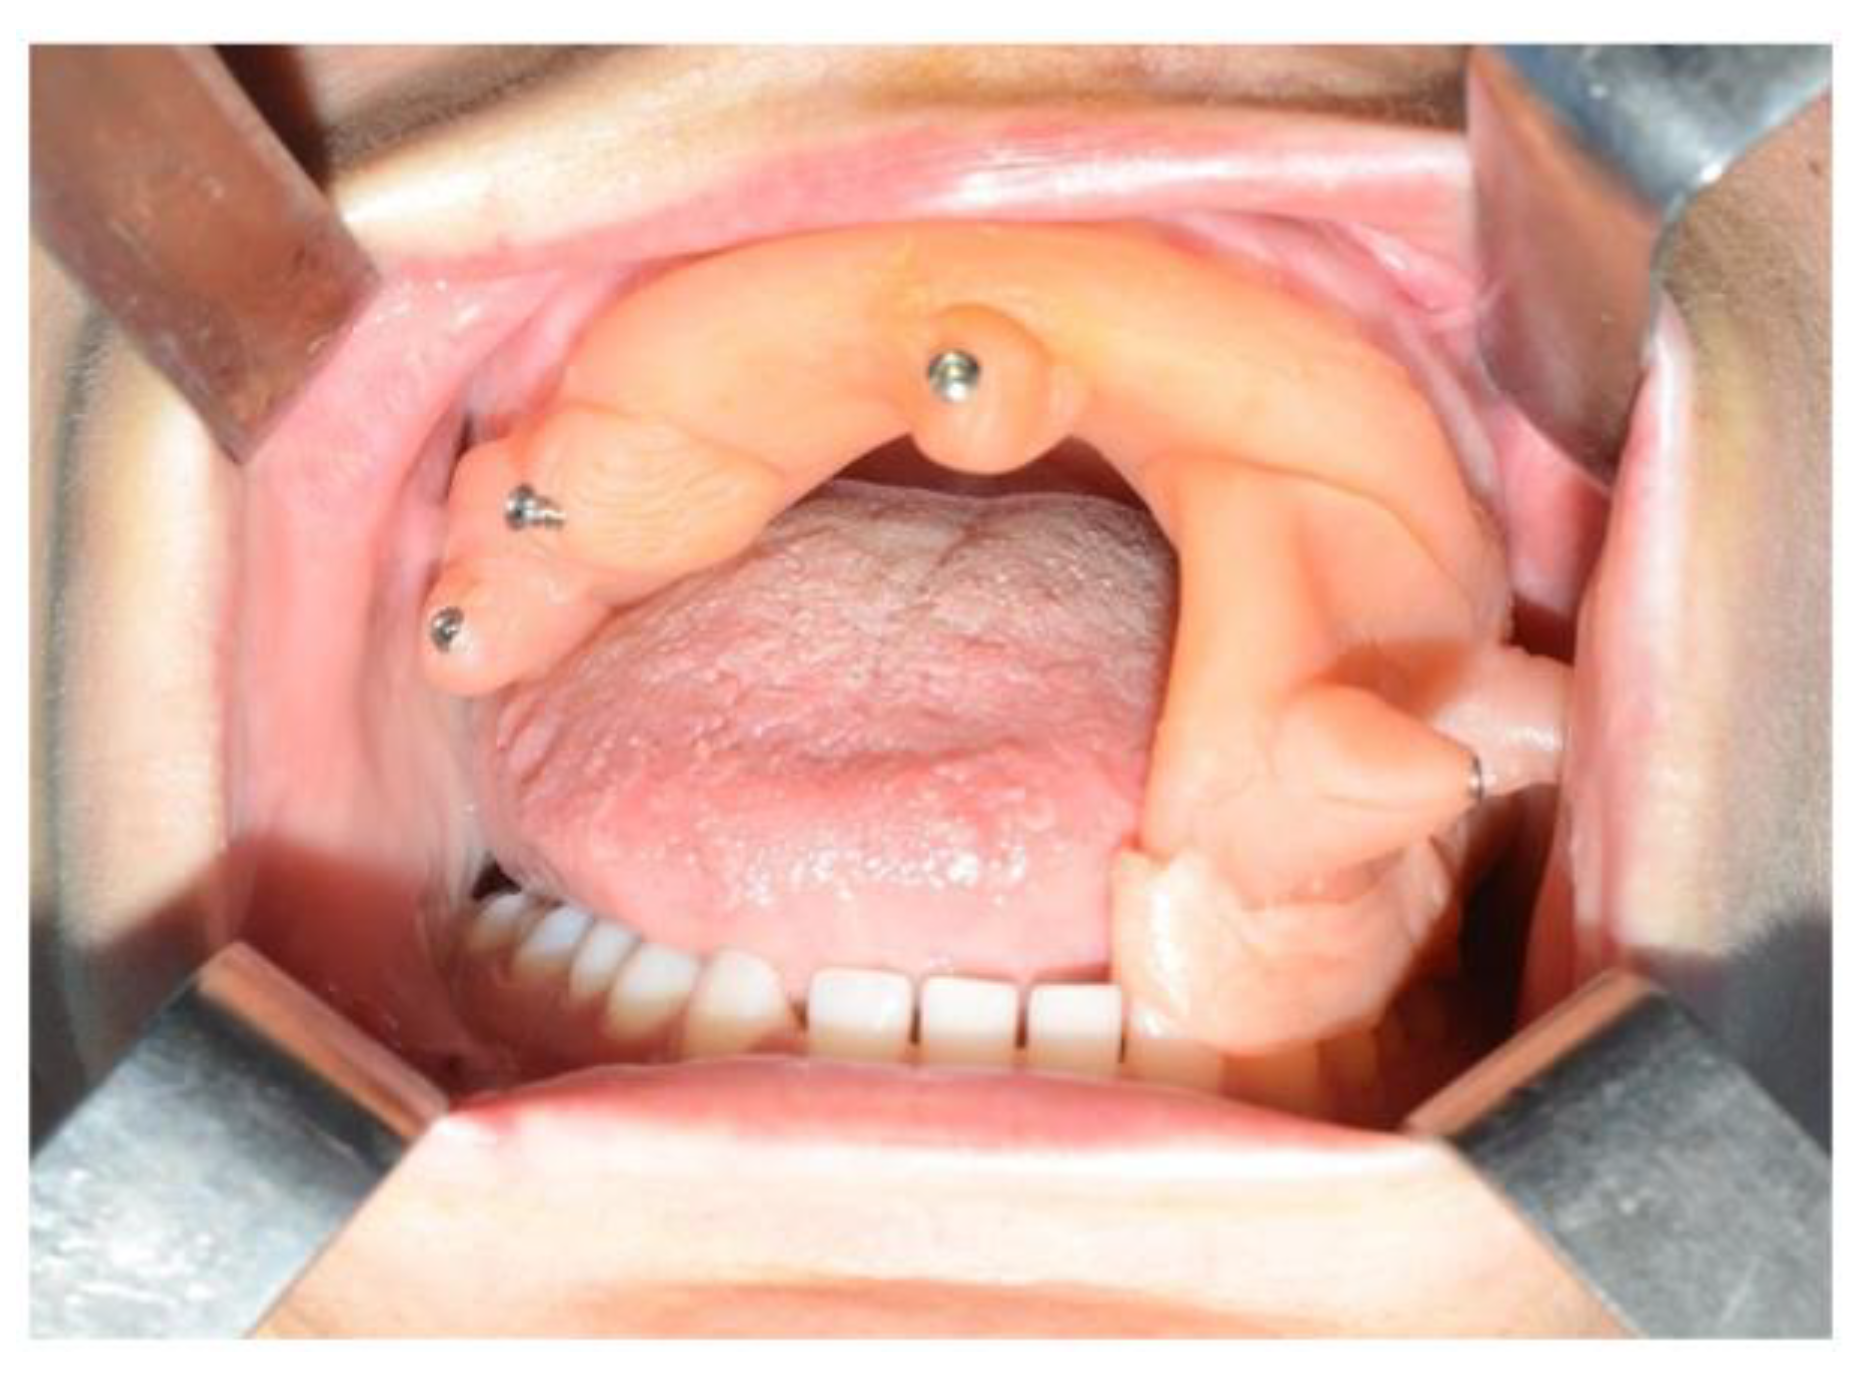

In light of the suspicion of an ameloblastoma recurrence, surgical removal was recommended, opting for the use of tracked instruments with surgical navigation. A maxillary bite was created, followed by the attachment of 5 screws with varying spatial orientations that would function as fiducial markers. This bite was employed to maintain the mandible in a consistent position both during the preoperative CT scan acquisition and throughout the entire surgical procedure (Figure 13).

Figure 13.

Intraoperative placement of the same bite used for acquiring mandibular CT scan images. The bite ensures the mandible remains in the same position as during the virtual surgical planning.

During the surgical procedure, the Dynamic Reference Frame (DRF) was positioned in the right parietal bone, and the positions of the screws on the bite were recorded as fiducial markers. The same bite used during the CT image acquisition was utilised for this purpose. The navigation accuracy was less than 0.5 mm. The piezoelectric was registered by attaching a tracking tool with three reflective spheres to the handpiece, and the tip of the piezoelectric was marked and utilised as a reference point for navigation. The navigation accuracy was found to be less than 1 mm.

Under the guidance of the tracked piezoelectric device, the resection of the lesion was carried out as per the preoperative plan, with macroscopically preserved healthy bone margins, including the lower and posterior mandibular border (Figure 14).